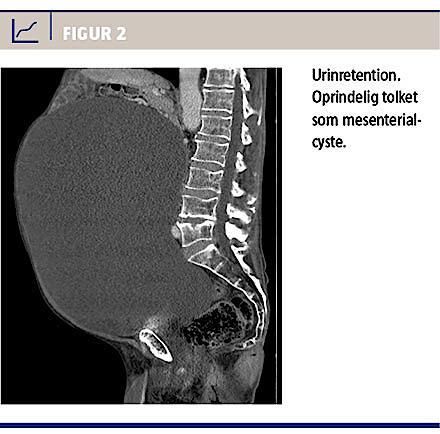

Endelig må det anbefales, at man ved fund af cystiske, abdominale processer altid overvejer urinretention som differentialdiagnose (Figur 2). Blæren kan være så stor, at man ikke kan få øje på den, og selv monstrøs retention kan forekomme uden større påvirkning af de øvre urinveje.